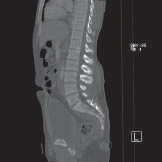

De CT-scanner (afgekort CT) is een apparaat dat door middel van röntgenstralen en een computer afbeeldingen maakt van uw organen, botten en weefsels. Zo’n afbeelding heet een CT-scan. Op een CT-scan is een dwarsdoorsnede van het te onderzoeken orgaan, bot of weefsel te zien. Hiervan kan op een computer achteraf een reconstructie worden gemaakt in een andere richting. Hieronder ziet u enkele voorbeelden van CT-scans.